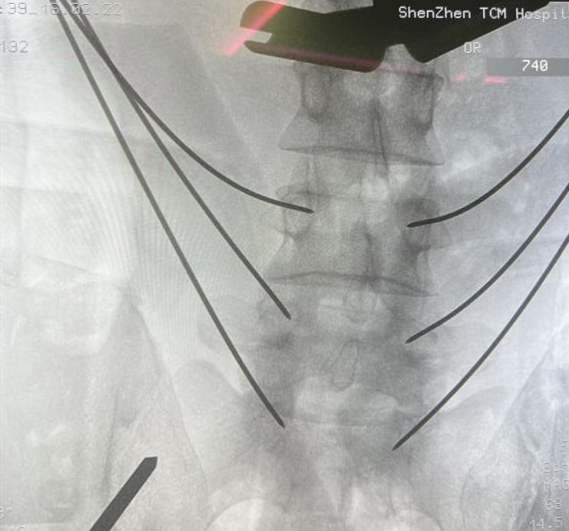

在骨科手术机器人的辅助下,通过术中3D影像图像进行精准置钉路径定位规划,手术团队结合既往开放手术的经验,顺利在椎弓根置钉通道完成精准置钉,螺钉及走行位置满意,然后再行融合技术。术后患者症状得到有效缓解。借助天玑III骨科手术机器人的辅助,精准、高效地完成了手术,手术出血不到150ml,术后生命体征平稳,双下肢感觉、运动正常,脊柱序列恢复满意。

天玑III骨科手术机器人辅助下置钉